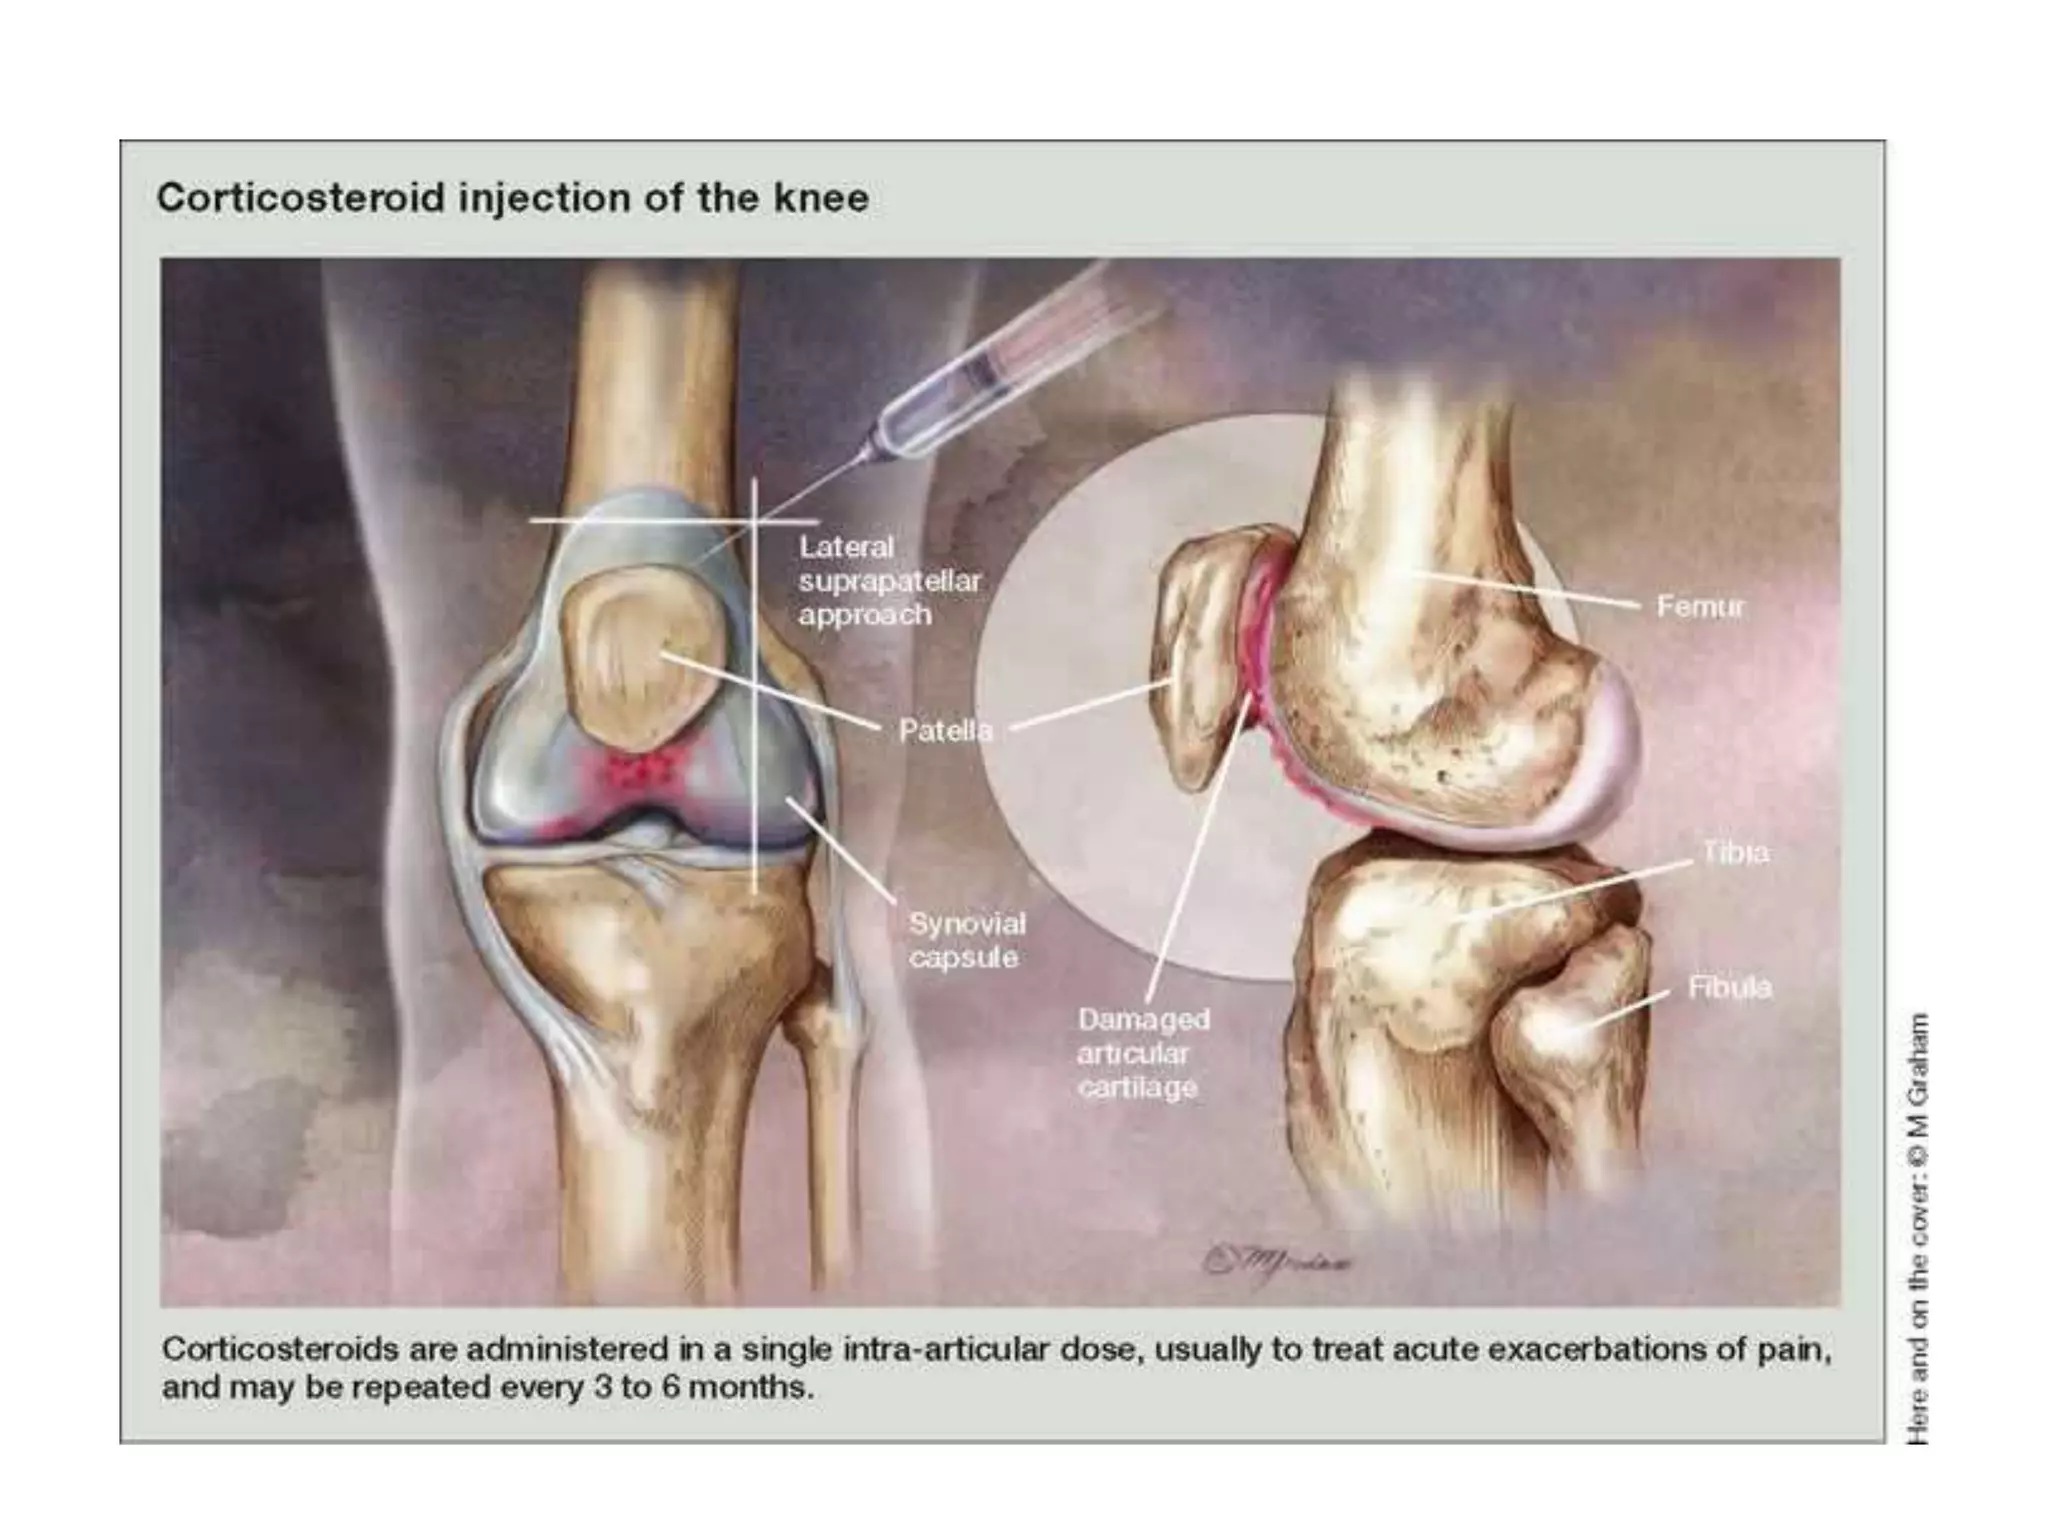

• INTRA ARTICULAR INJECTIONS

Intra-articular injections